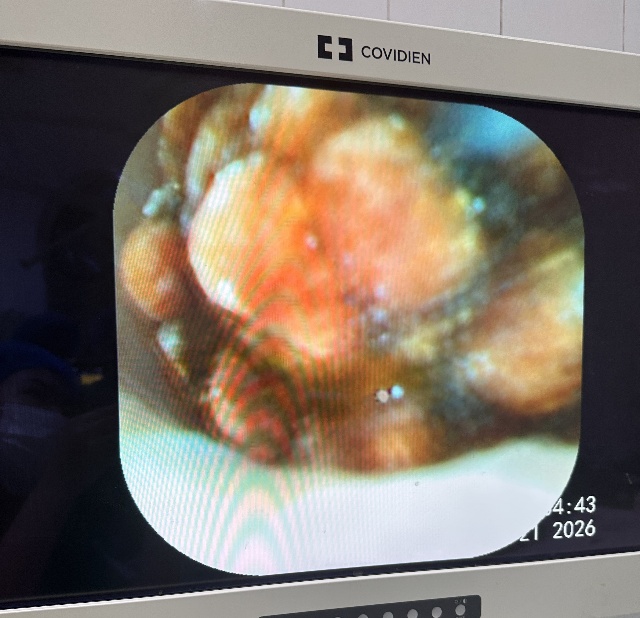

Bn nữ 44 tuổi đau thượng vị nhiều đợt. Đi khám và được chẩn đoán xơ teo thùy gan trái do sỏi gan trái. Sau hội chẩn được chỉ định cắt thùy gan trái nội soi. Trong ca mổ chung tôi đã sử dụng dao hàn mạch Ligasure và Stapler để tiến hành cắt gan trái cho bệnh nhân. Ca mổ đã diễn ra thuận lợi không chảy máu. BN ra viện sau 7 ngày.

Hình ảnh sỏi và phần gan được cắt bỏ qua nội soi.